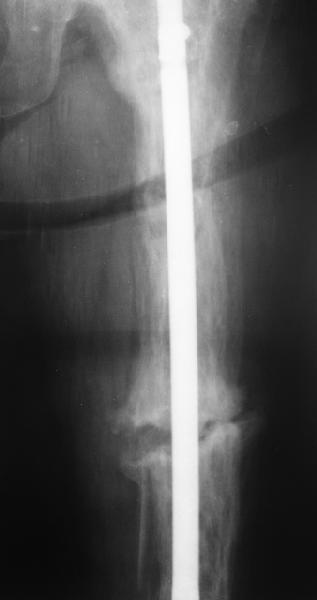

Пациент 82 лет, поступил через 5 мес. с несросшимся переломом после открытого интрамедуллярного остеосинтеза. Выполнили реостеосинтез стержнем 12 мм. ( мах. доступного нам в 2003 г.) Через 4 мес динамизация. В течении 2х лет сращения нет, тем не менее конечность опорна (ходит с тростью). От очередного реостеосинтеза отказались из-за сопутств. патологии.

PS: случай конечно не аналогичный, учитывая первичный открытый остеосинтез.